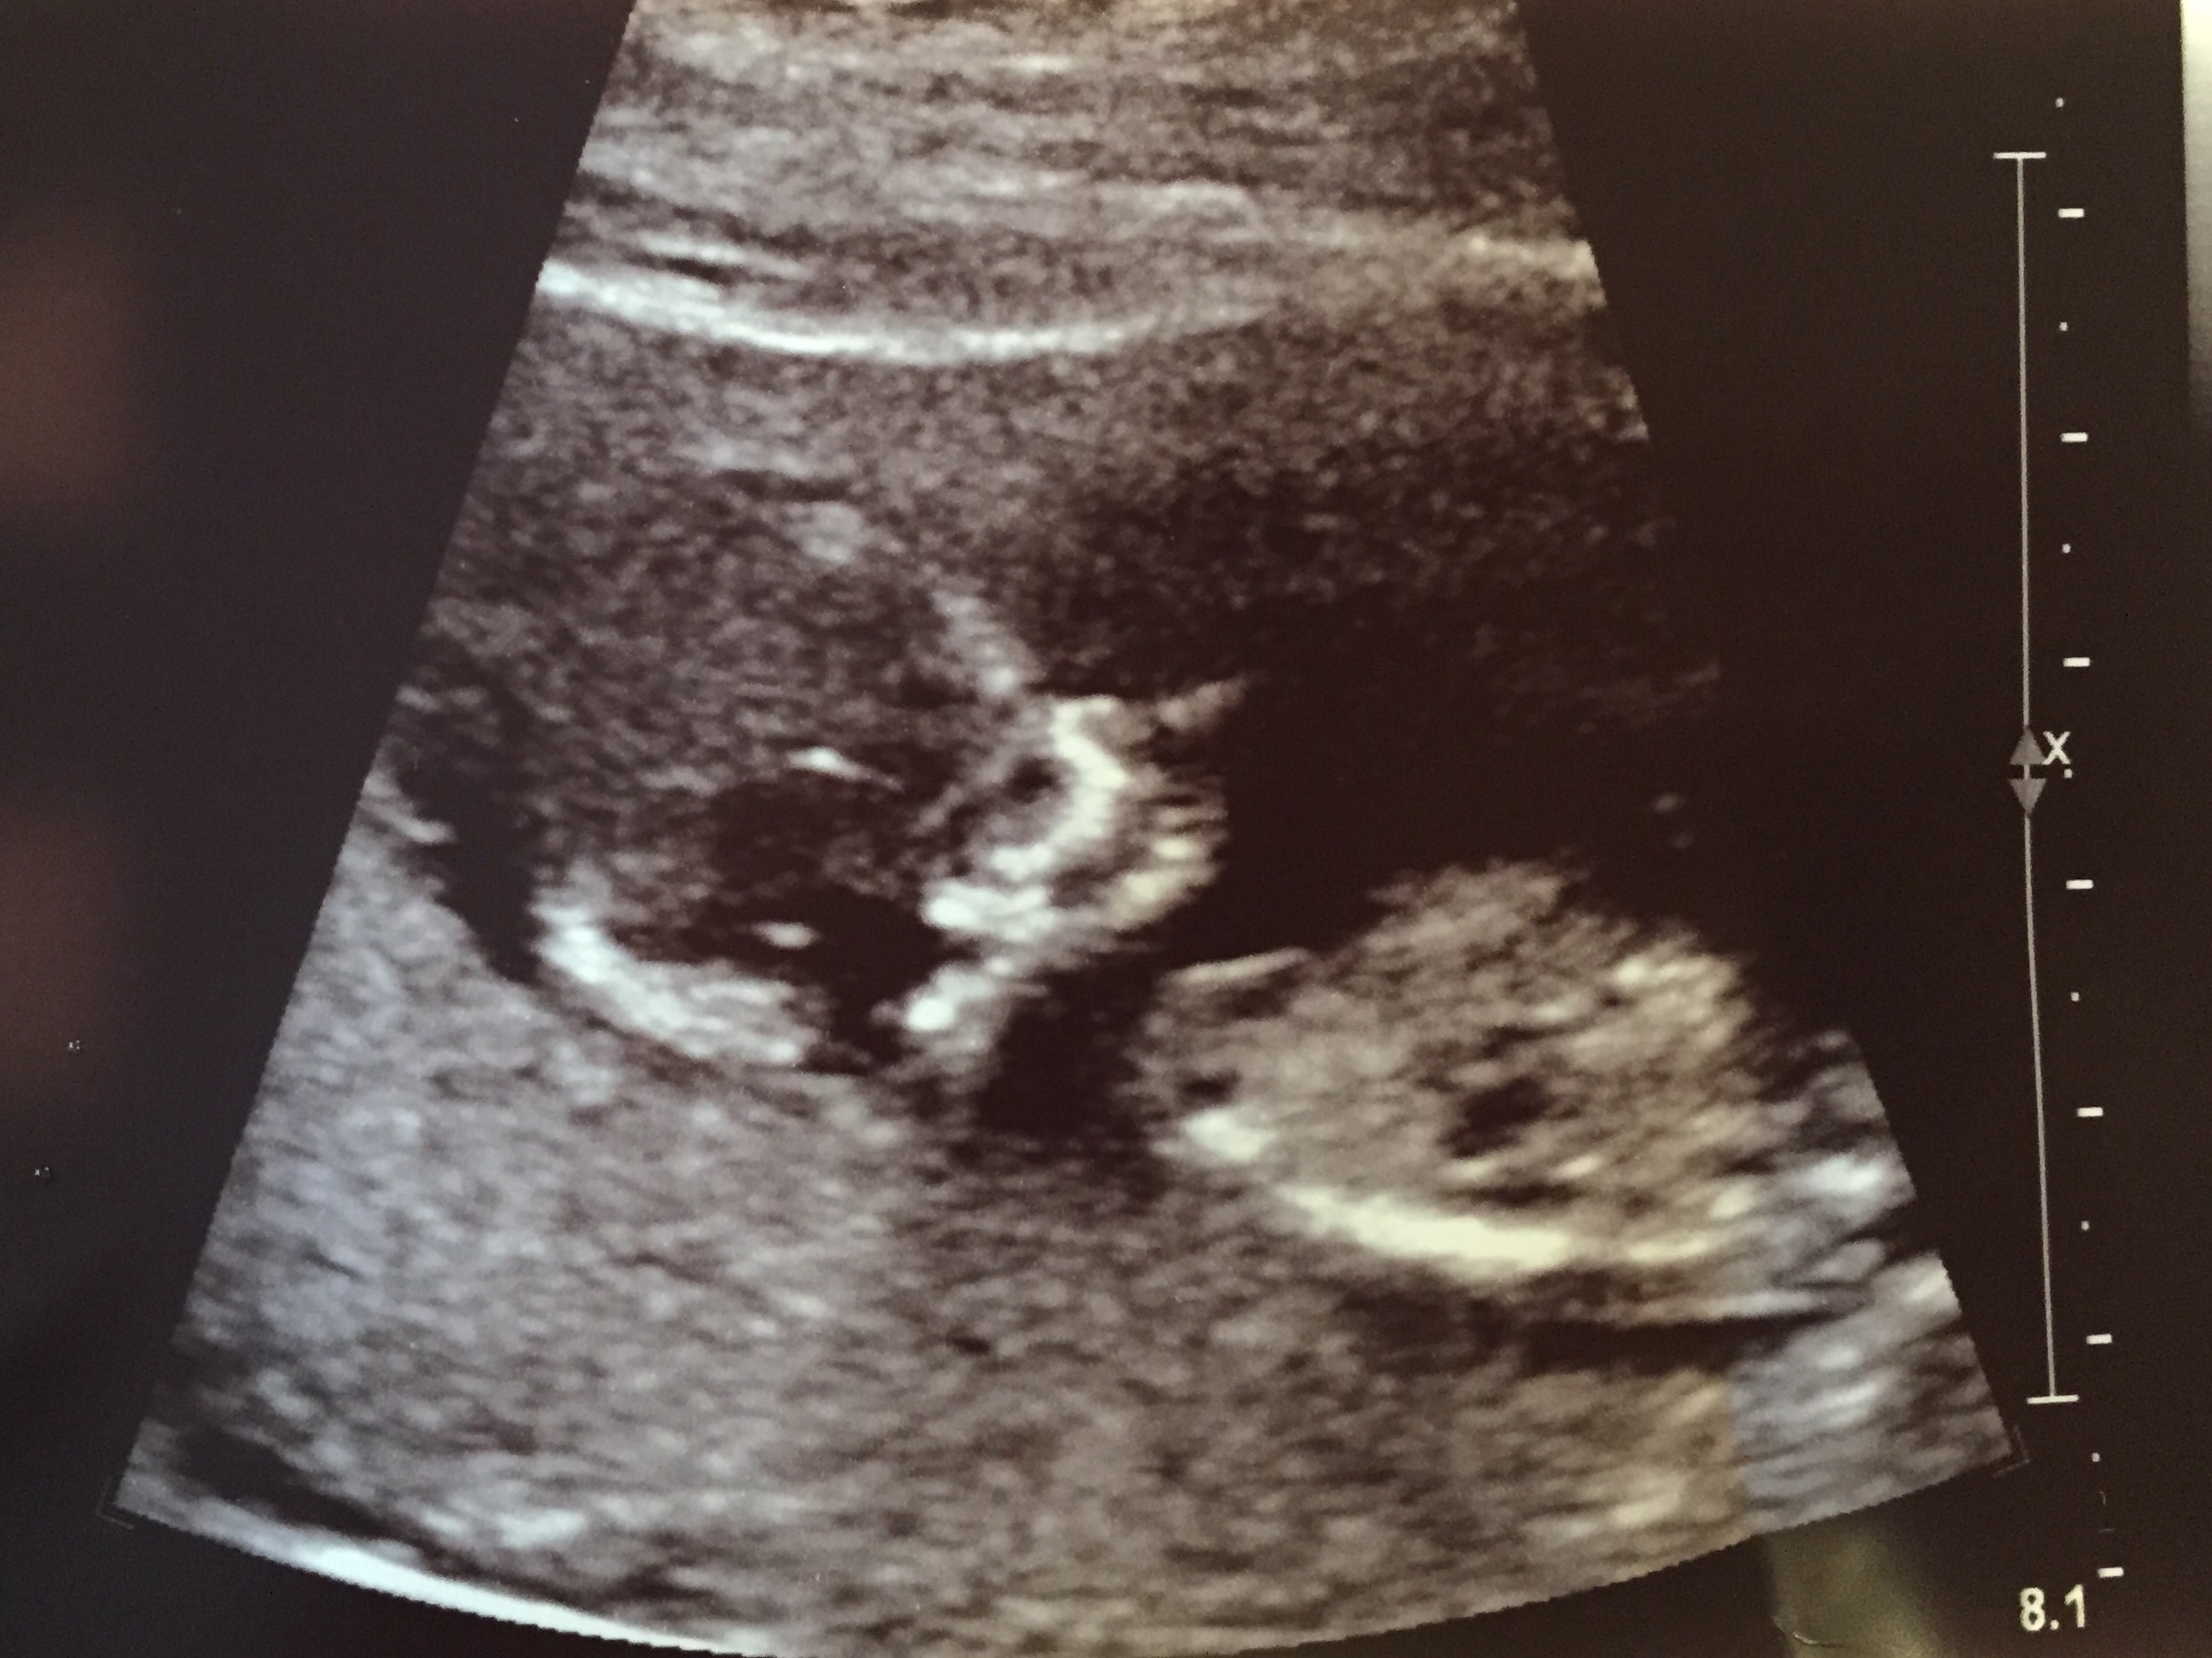

I had my 12 week ultrasound today! I went in at 12 weeks 3 days but they moved me to 12 weeks 6 days due to size and estimation from the first day of my last period they felt this due date was more accurate. Due October 14 2015 now! I am a FTM so wi still probably go late though!